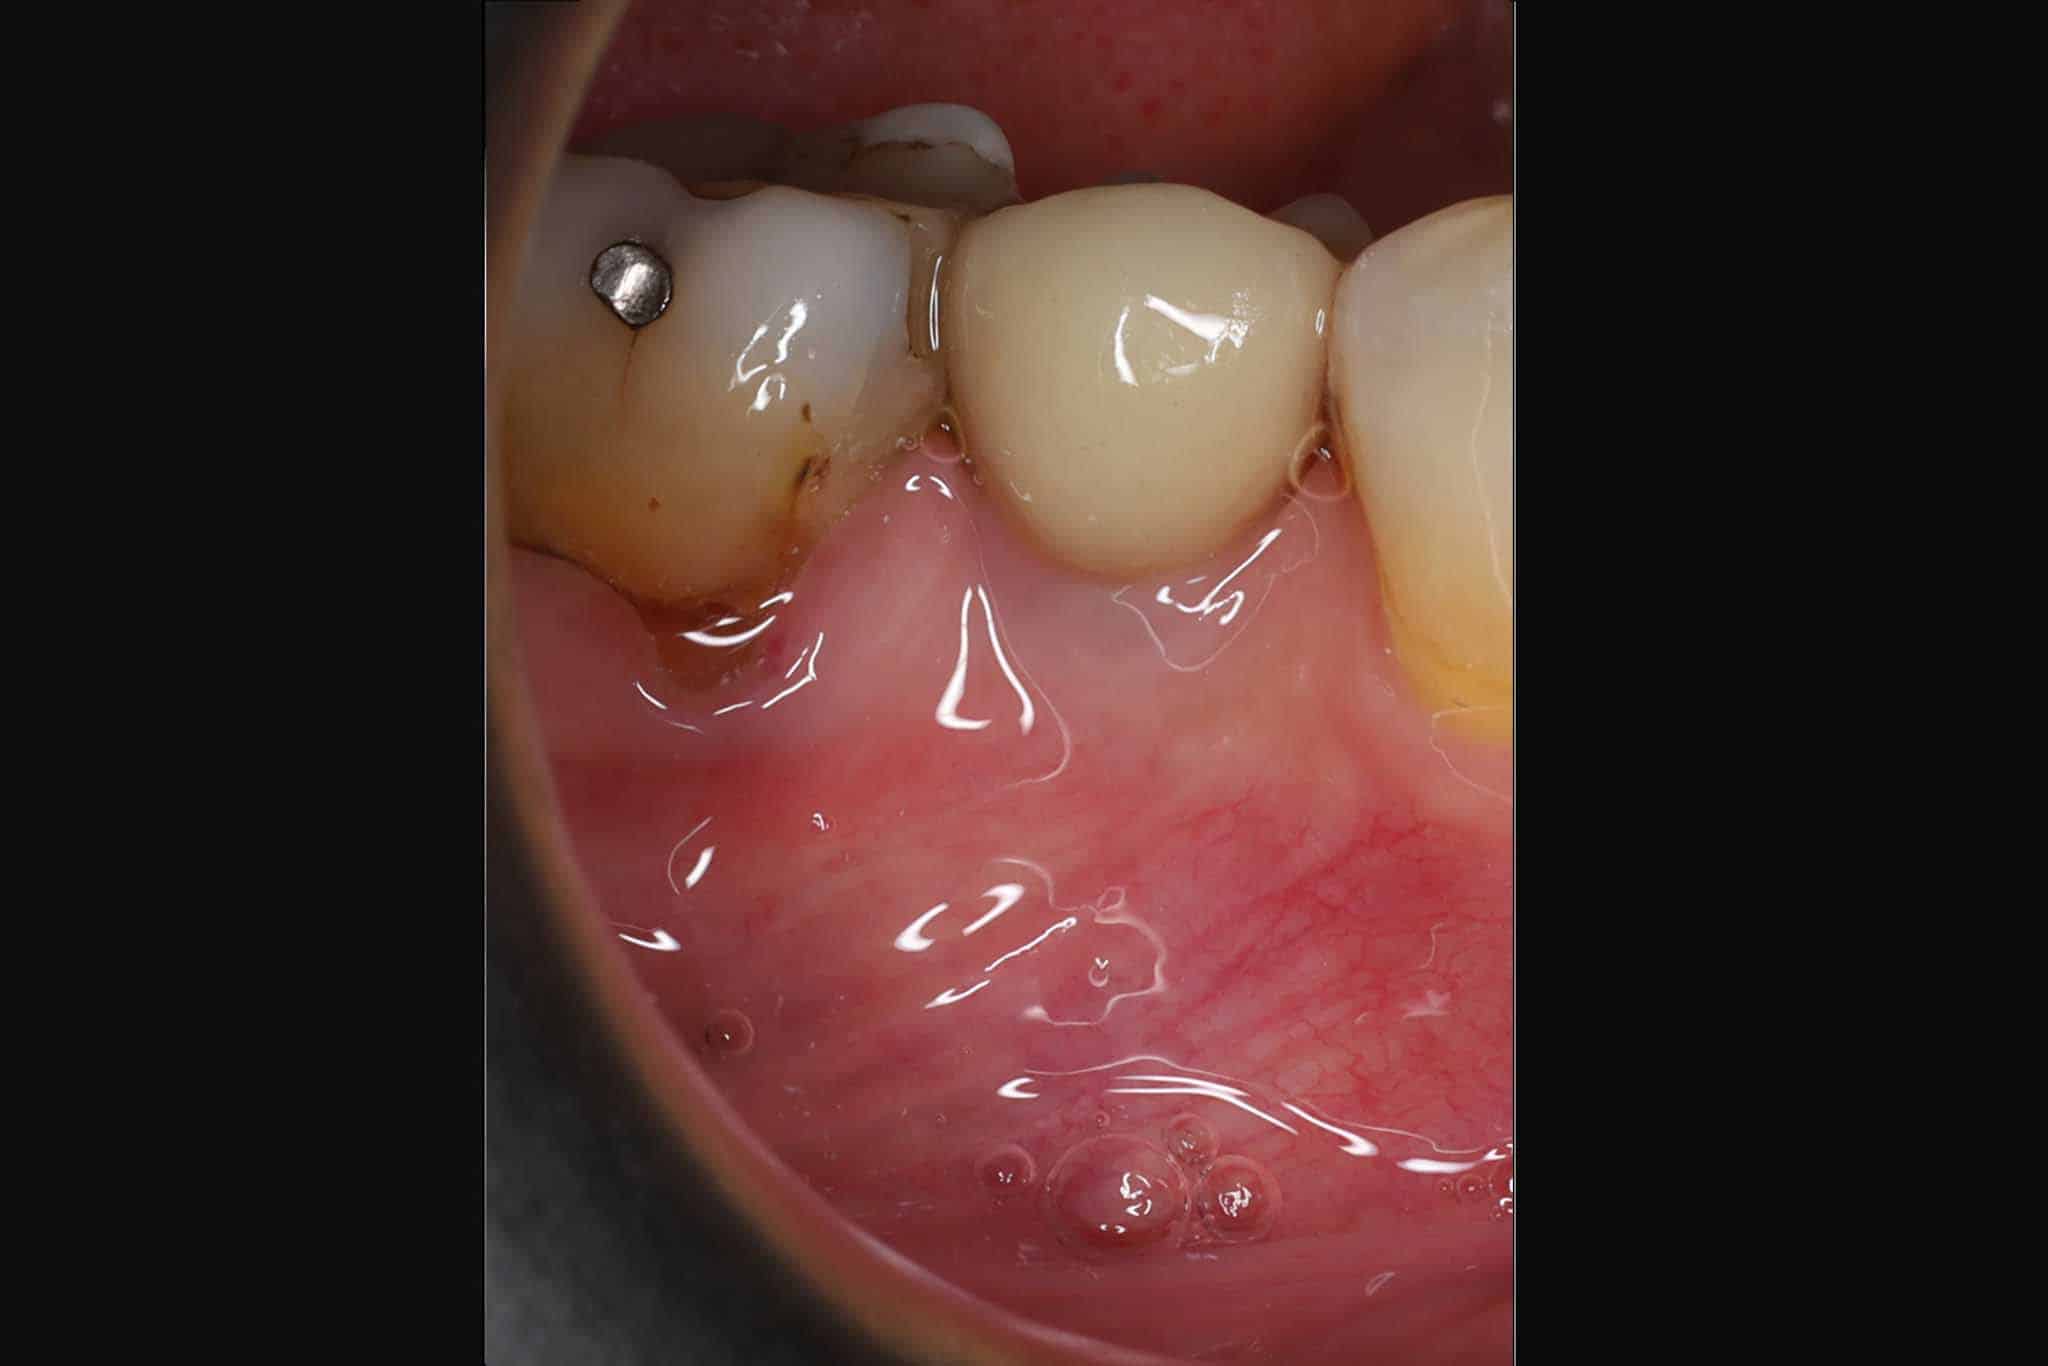

Før- og etterbilder av tannimplantater – Se våre pasientresultater

Flere bilder